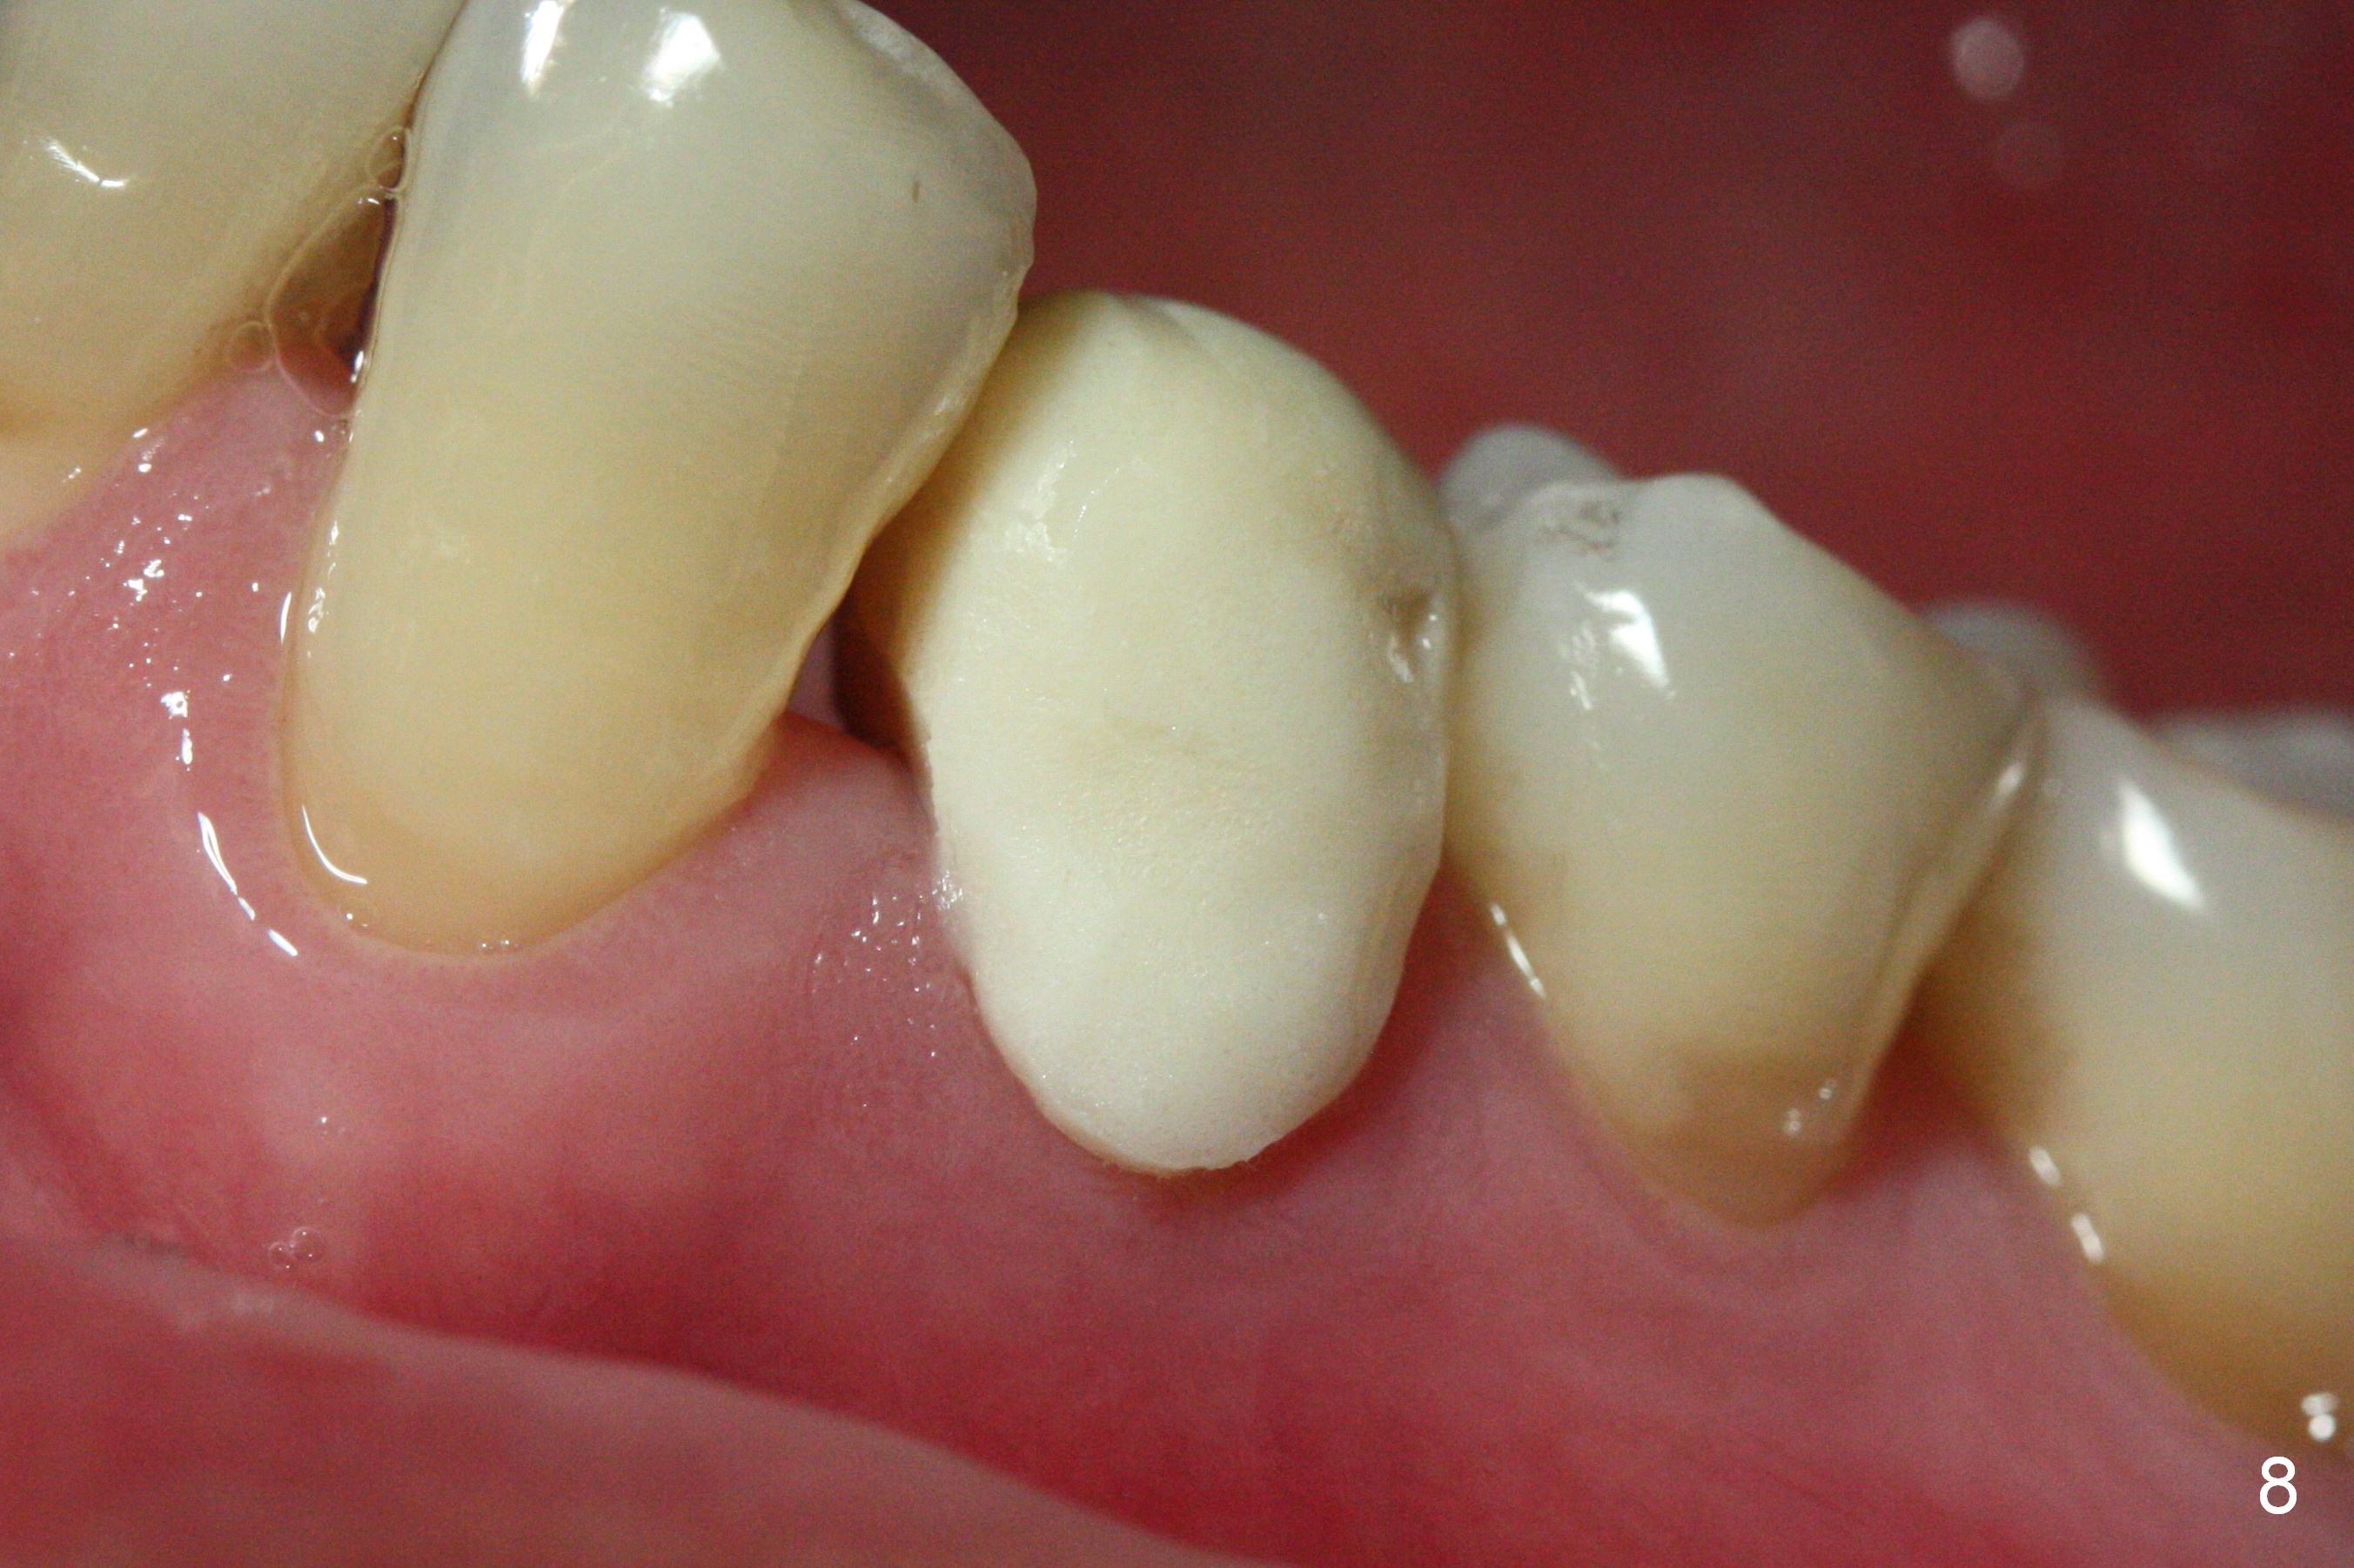

The patient returns for provisional revision 2 weeks postop (Fig.6). The bone graft remains in place (Fig.7). The buccal margin of the provisional is reduced (Fig.8).

The implant seems to have osteointegrated 4 months postop (Fig.9). When a permanent crown is fabricated, it should have normal occlusal and buccal contour (from Fig.11 (provisional) to 12 red and black curved lines) as well as the buccal cervical extension (Fig.12 to cover the buccal gingiva (Fig.10 *). If the lingual margin of the abutment is too prominent, return the case and the abutment will be changed to the one with 2 mm cuff (existing 3 mm). The lingual margin of the abutment will be trimmed. The patient is not pleased with the short buccal margin of the crown after cementation (Fig.13). In fact the provisional should have been fabricated so that the its buccal margin should be subgingival and within the gingival outline. It may prevent buccal plate collapse. In fact the crown dislodges 1 year post cementation. The lingual margin is prep lower to increase the abutment height. Impression is taken. Although the access hole is unnecessary for cementation, it acts as an escape hole so that there is no excess cement cervically (Fig.14-18).